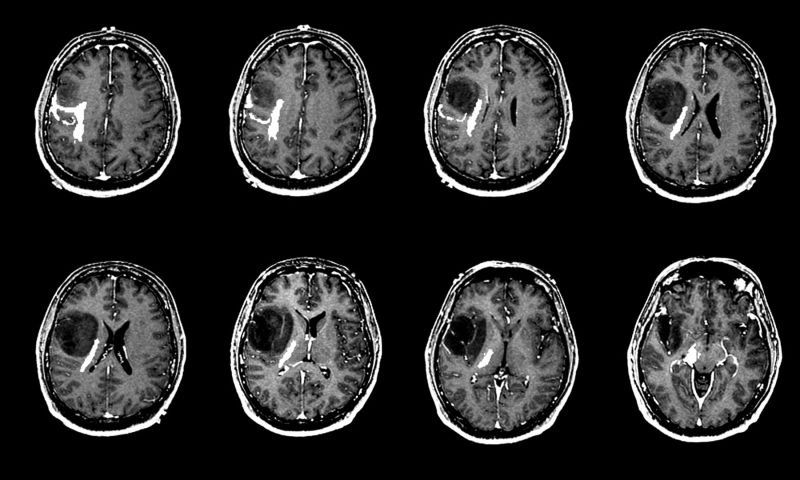

Chụp cộng hưởng từ MRI

MRI sử dụng từ trường thay vì tia X để tạo ra hình ảnh chi tiết của cơ thể. Ưu điểm của phương pháp MRI là có thể đo được kích thước của khối u. Cũng giống như phương pháp chụp CT kể trên, các bác sĩ cũng đưa vào cơ thể bệnh nhân thuốc cản quang trước khi bắt đầu quét hình ảnh. Bệnh nhân được tiêm thuốc vào tĩnh mạch hoặc uống thuốc.

Có cách nào chẩn đoán u tế bào mầm ở trẻ em không - Tìm hiểu ngay! 2 Chụp MRI thường được dùng để xác định khối u khi đã di căn lên não